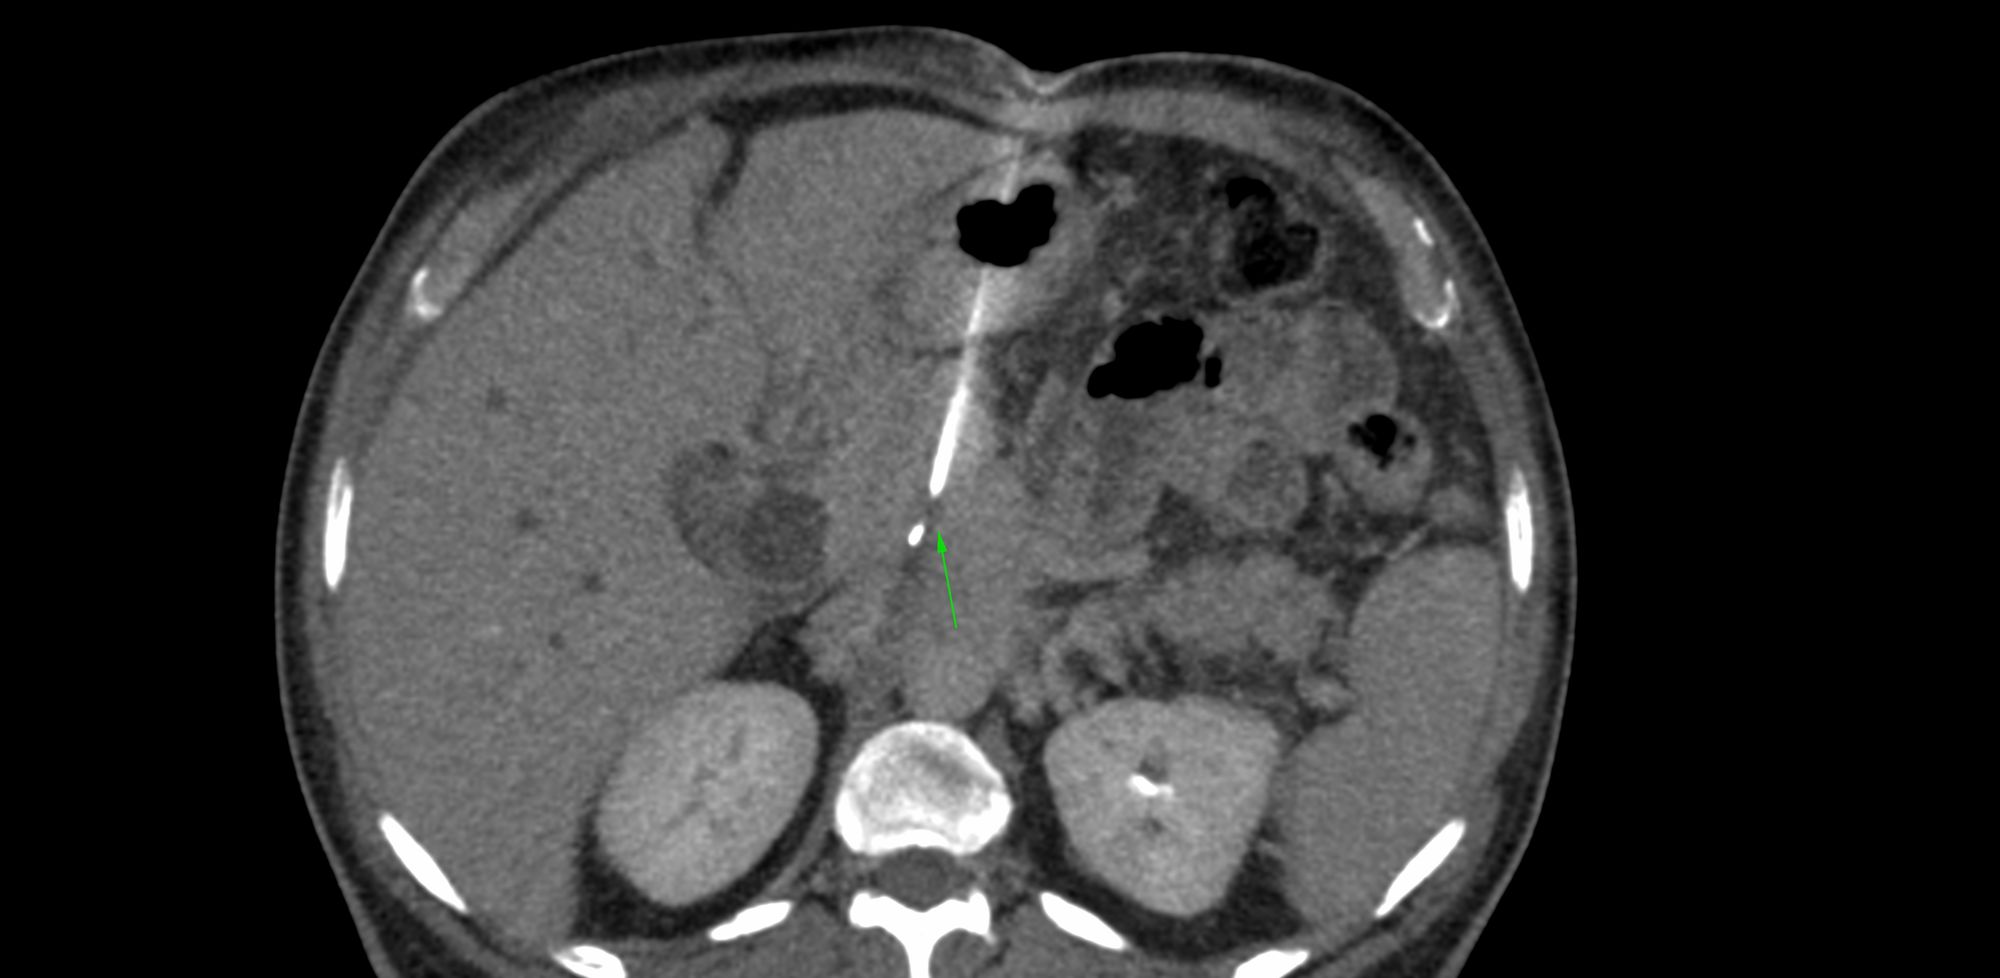

Case 89: Biopsy of Retroperitoneal Fibrosis